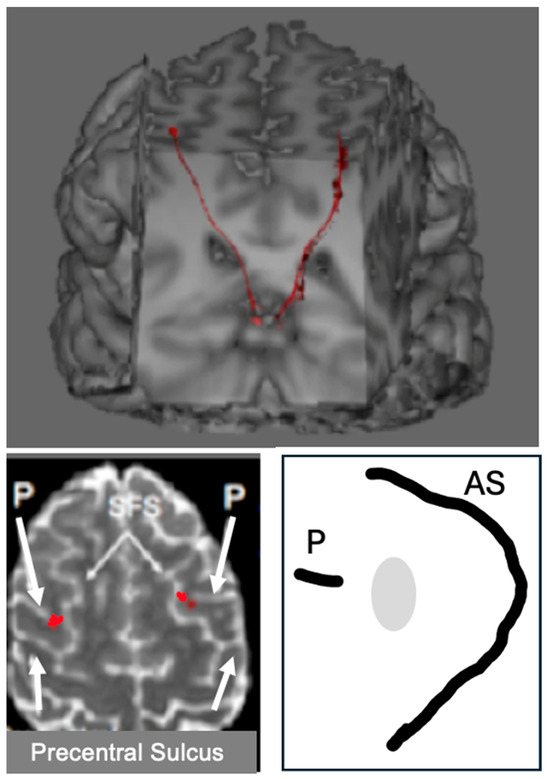

Figure 1 shows an adaptation of a drawing published by Rezso Bálint (1909) showing the regions of both parietal lobes damaged in a patient manifesting a syndrome bearing his name (Husain and Stein 1988). These strokes had damaged the dorsal visual stream bilaterally. Arrows have been added to show the intraparietal sulcus that divides the parietal lobe into the inferior and superior lobules.

The intraparietal cortex, which surrounds the intraparietal sulcus, receives and maintains a retinotopic map of visual information transmitted from the primary visual cortex (Silver et al. 2005). As we shall see, in the intraparietal cortex, these visual signals are integrated with copies of motor commands to move the eyes and upper limbs. Damage to intraparietal cortex causes a bilateral disintegration of these two sources of information and engenders a catastrophic derangement of perception and visually guided behavior that manifests as Bálint’s syndrome.